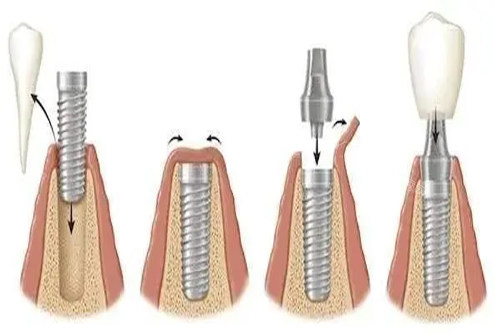

数字种植牙通过CBCT扫描、口内光学扫描获取三维口腔数据,生成虚拟模型后进行术前规划,并利用3D打印导板引导种植体植入。传统种植牙则依赖医生经验,通过物理模型和X光片判断种植位置,依赖手工操作完成植入。

物理模型:

通过石膏模型和X光片评估口腔状况,依赖医生对解剖结构的理解。

手工操作:

医生通过切开牙龈、翻瓣、缝合等步骤完成种植,对医生经验要求较高。

切开翻瓣:

需切开牙龈、翻开软组织,暴露牙槽骨后植入种植体,创伤较大。